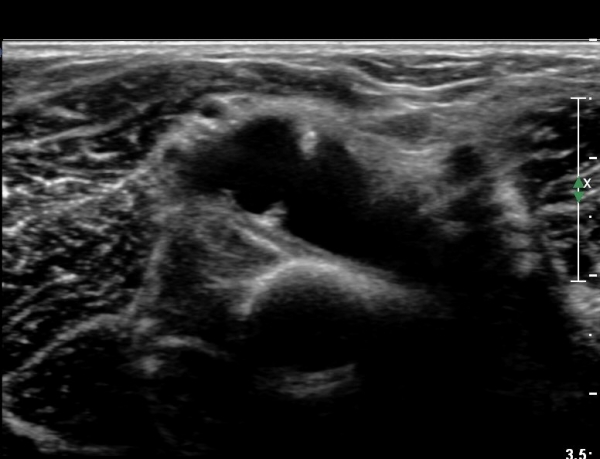

out of plane À¸·Î ³¶Á¾ ÈíÀÎÀ» À§ÇØ ÁÖ»ç¹Ù´ÃÀÌ ³¶Á¾³»¿¡ À§Ä¡ÇÑ ¸ð½À(»çÁø 8)

³¶Á¾ ÈíÀÎ ÈÄ ³¶Á¾ÀÌ °ÅÀÇ º¸ÀÌÁö ¾Ê´Â ¸ð½À(»çÁø 9, 10)